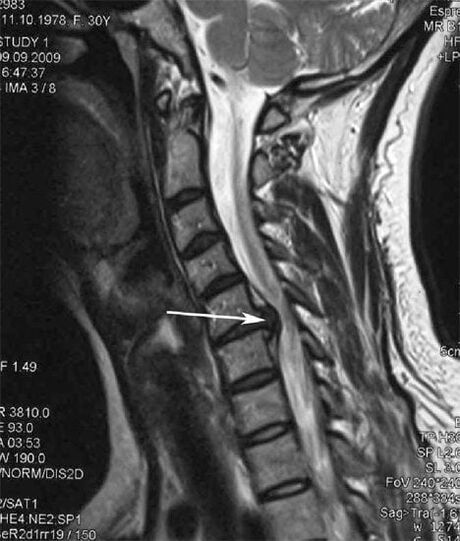

На пачатковых стадыях астэахандроз выяўляецца з дапамогай МРТ. Пазней паталогію можна дыягнаставаць з дапамогай рэнтгенаграфіі. На рэнтгенаграмах шыйнага аддзела хрыбетніка прыкметныя памяншэнне адлегласці паміж пазванкамі, паталагічныя змены фасеткавых суставаў, остеофитоз.

Многія скардзяцца на тое, што не могуць павярнуць шыю з-за моцнай болю, якая з'яўляецца пасля раптоўнага ўзняцця чаго-небудзь цяжкага. Гэта з'ява сведчыць аб адукацыі кілы дыска. Прычынай боляў у спіне, шыі і верхніх канечнасцях з'яўляецца зашчымленне аднаго з нервовых карэньчыкаў, якія адыходзяць ад спіннога мозгу.

| Шыйны астэахандроз | З'яўленне паталагічных змен у адным або некалькіх спінна-рухальных сегментах. Парушэнне рухомасці пазваночніка, развіццё миофасциальных болевых сіндромаў і зашчымленне спіннамазгавых карэньчыкаў. | Боль, парэстэзіі і рухальныя парушэнні ў шыйным аддзеле, якія распаўсюджваюцца на патыліцу і верхнія канечнасці. Выяўленне характэрных змяненняў у пазваночніку на МРТ і рэнтгенаграме (остеофиты, памяншэнне адлегласці паміж пазванкамі, прыкметы паразы межпозвонковых суставаў) |